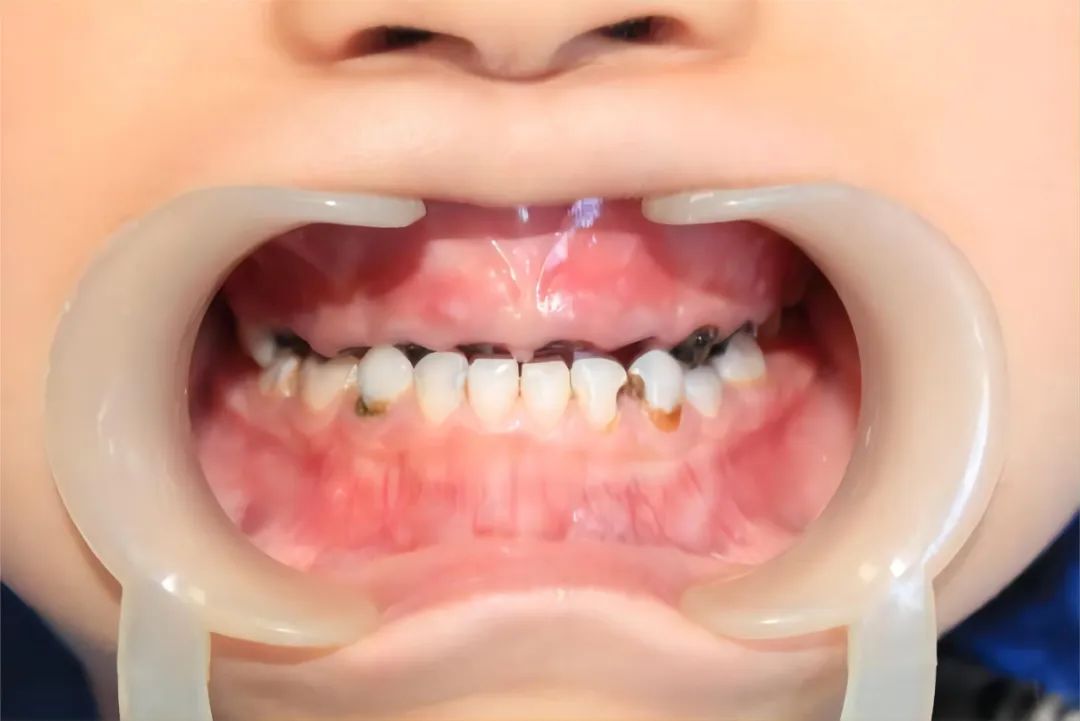

那这个时候你查的可能不是错颌畸形,你可能查的是口腔卫生好不好啊,比如说我注意到有很多孩子,一来到门诊检查满嘴都是坏牙,这个是需要关注的点。

孩子习惯晚上睡觉前喝牛奶,含着奶瓶入睡,还有爱吃含糖量高、奶制品的零食等等,所以这是很多小孩牙齿龋坏的一个最重要的原因。

当这个孩子一旦发生龋坏的时候,错颌畸形跟着就会出来,我的反颌问题就是小时候牙坏的特别多,吃东西只能往前伸,慢慢发展为反颌。